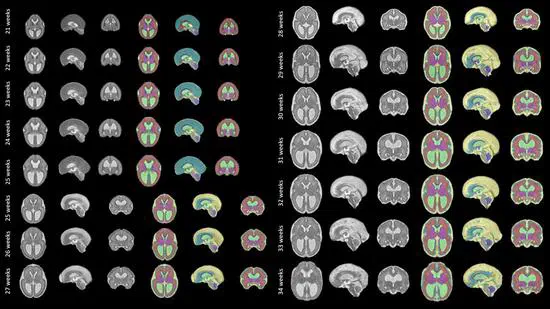

We make publicly available a spatio-temporal fetal brain MRI atlas for SBA. This atlas can support future research on automatic segmentation methods for brain 3D MRI of fetuses with SBA.

NiftyMIC is a Python-based open-source toolkit for research developed within the GIFT-Surg project to reconstruct an isotropic, high-resolution volume from multiple, possibly motion-corrupted, stacks of low-resolution 2D slices. Read “Ebner, M., Wang, G., Li, W., Aertsen, M., Patel, P. A., Aughwane, R., … & David, A. L. (2020). An automated framework for localization, segmentation and super-resolution reconstruction of fetal brain MRI. NeuroImage, 206, 116324 (📖).”